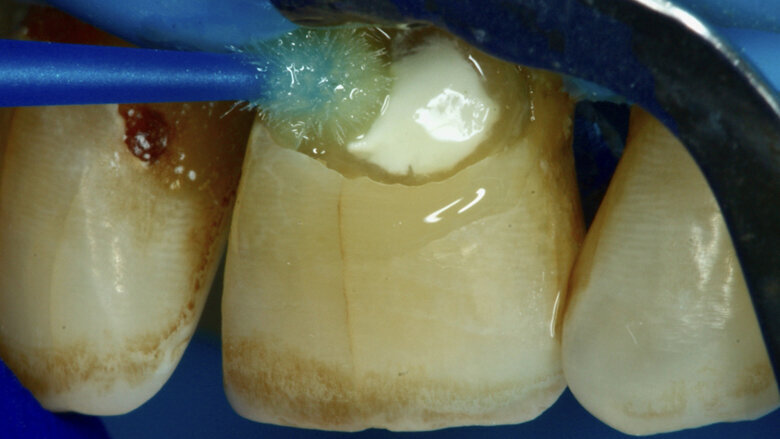

Paciente masculino de 65 años de edad se presenta al consultorio con lesiones de caries cavitadas en dentina activa (ICDAS 5) en dientes 11 y 21 (Figura 1). La lesión de la pieza 21 es extensa, mediante examen radiográfico y pruebas de vitalidad se diagnostica ausencia de compromiso pulpar. Como la lesión se extiende infra-gingivalmente, se opta por colocar dos hilos retractores 000 y 00 (Ultrapack, Ultradent, EE UU) y aislamiento absoluto con hilo dental tipo teflón y un clamp para anteriores (Figuras 2 y 3). Se inicia el procedimiento de remoción químico-mecánica utilizando un agente enzimático (Brix3000, Brix Medical Science, Argentina) durante 2 minutos (Figura 4). Utilizando curetas (Maillefer, EE UU) se elimina la dentina infectada (Figura 5) y el esmalte sin soporte dentinario (Figura 6) es eliminado con una fresa multilaminada (Figura 7) para mejorar el mimetismo y la adhesión al esmalte. Se complementa la instrumentación mecánica en el límite amelo-dentinario (Figuras 8 y 9).

La cavidad es lavada con un micro-cepillo con piedra pómez y clorhexidina 0,12% (Figura 10) para colocar silicato de calcio modificado por resina (Theracal LC, Bisco, EE UU) por la proximidad a la pulpa (Figuras 11 y 12). Se condiciona el esmalte mediante la técnica de grabado selectivo (Figura 13) y se utiliza un adhesivo self-etch de dos pasos (Figuras 14 y 15), se adiciona la resina compuesta (Forma, Ultradent, EE UU) y finalmente se realiza el protocolo de pulido (Figura 16). La restauración finalizada se presenta en la Figura 17 y al remover el aislamiento en la Figura 18.